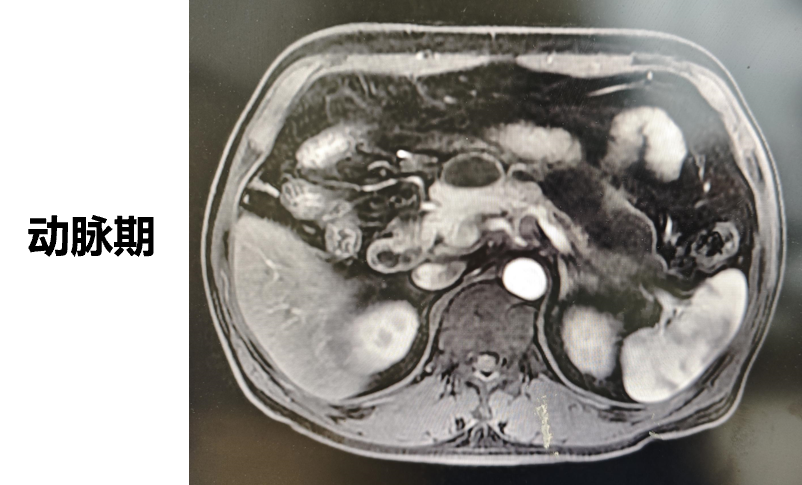

◈ 2022-7-19腹部MR增强扫描:提示T2WI及DWI胰腺体尾部信号稍高并胰管局限性稍扩张,肠系膜上动脉、腹腔干近段局部管壁增厚,需鉴别免疫相关性疾病累及或其他。

2022-7-19 上腹部MR增强扫描